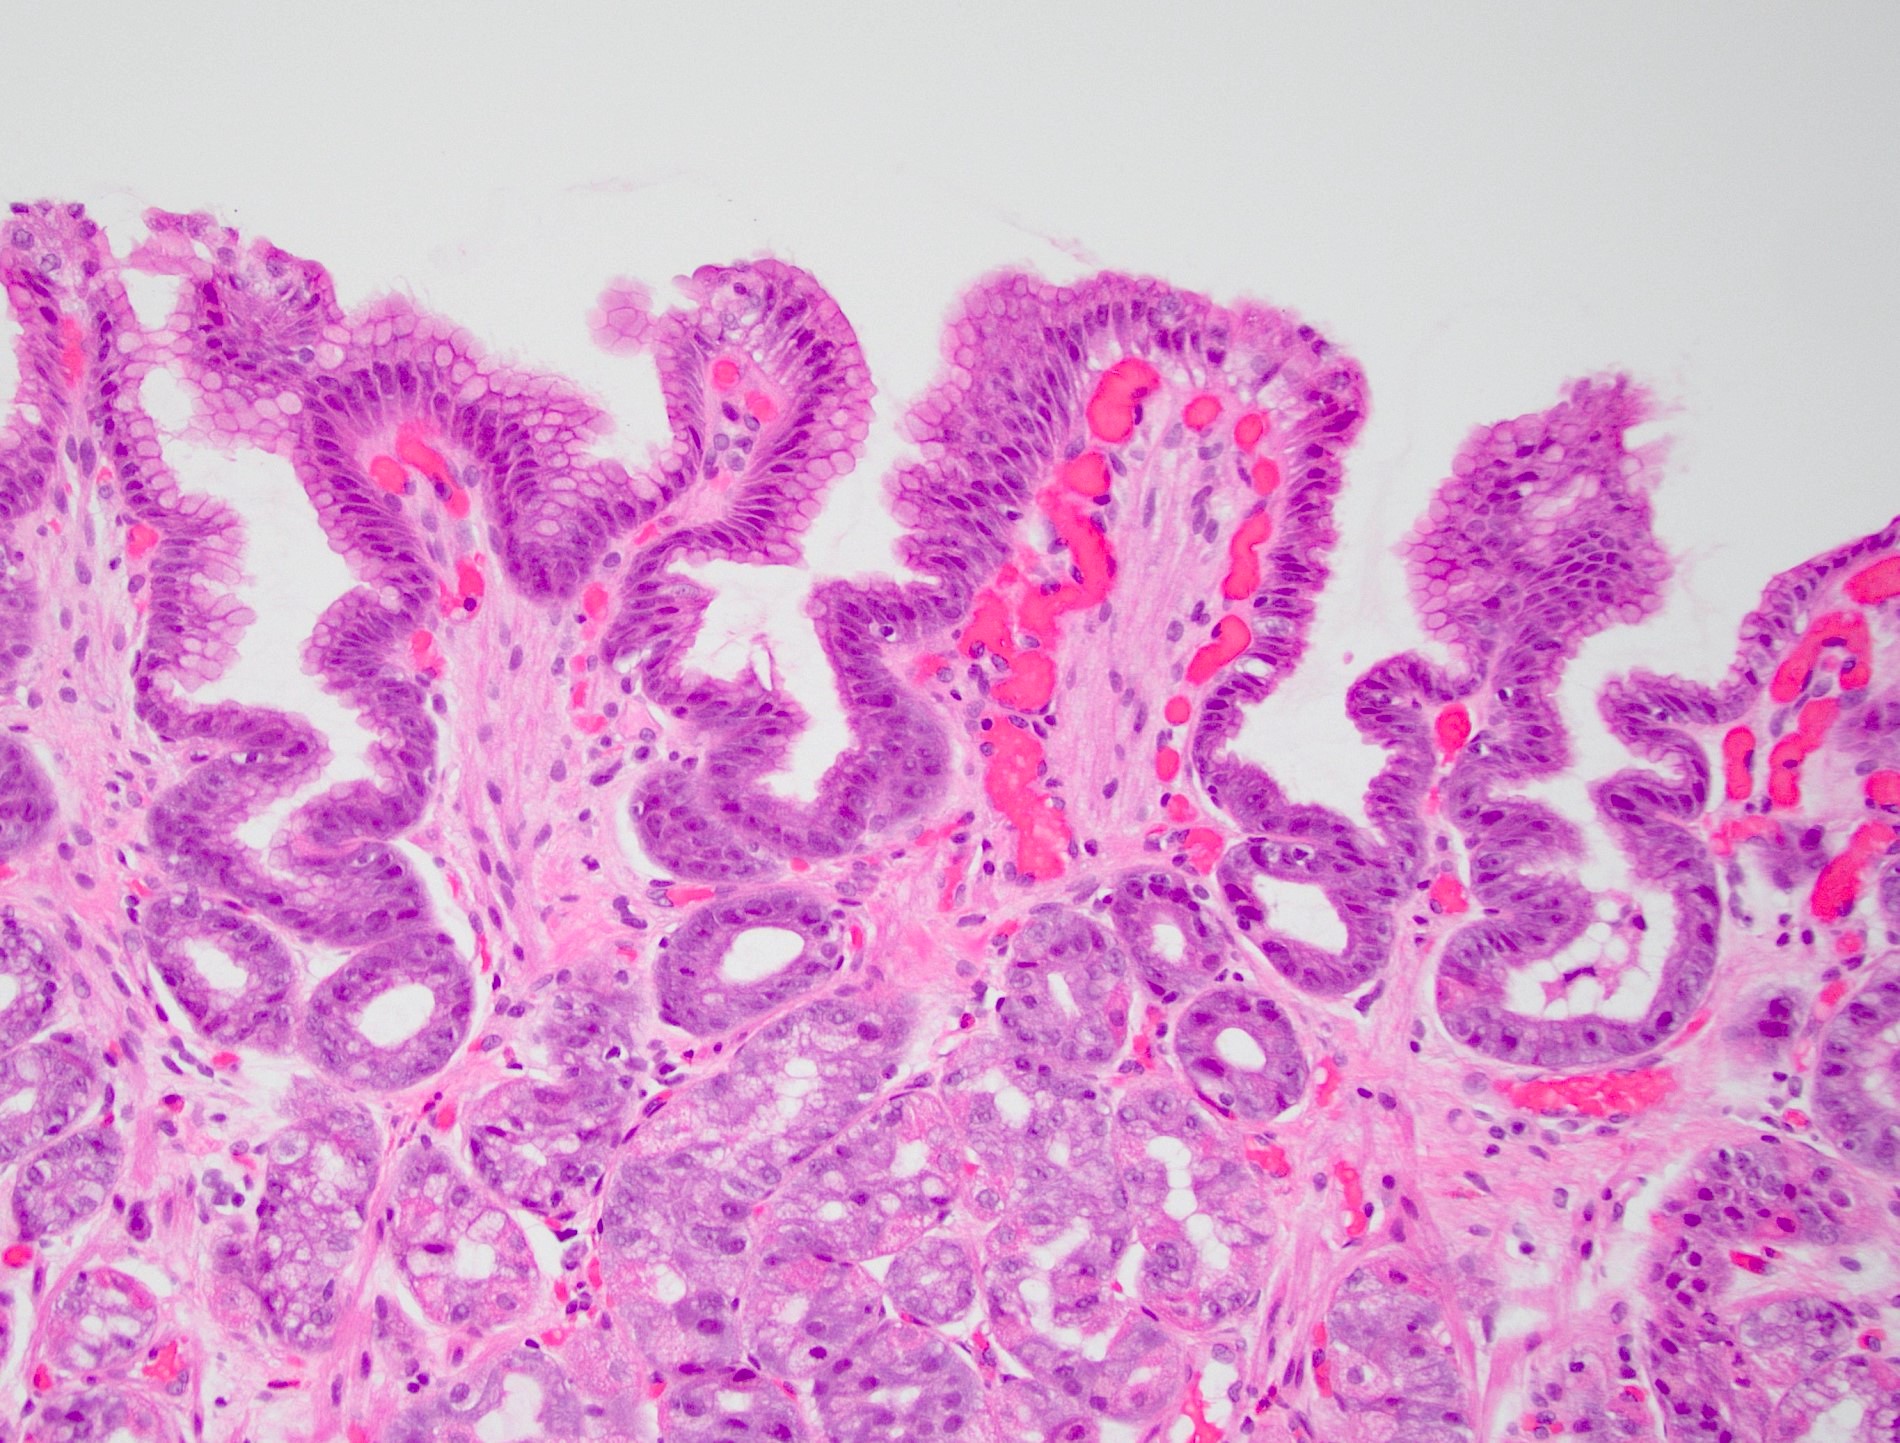

- Histology is characterized by foveolar hyperplasia, mucin depletion in surface epithelial cells and lamina propria expansion by fibromuscular and capillary hyperplasia

Microscopic (histologic) description

- Lack of significant edema or inflammation

- Foveolar hyperplasia: tortuosity / corkscrew appearance with a minimum twofold elongation of gastric cardiac foveolae and pits

- Mucin poor columnar cells with enlarged, hyperchromatic nuclei

- Lamina propria expansion with fibromuscular proliferation and congested, ectatic capillaries

Microscopic (histologic) images

A 48 year old woman with rheumatoid arthritis presents with dyspepsia and bloating. Endoscopy shows erythematous mucosa. Histopathology is significant for serrated gastric pits, foveolar hyperplasia, paucity of mucin in surface epithelial cells and ectatic superficial capillaries (see image). What is the diagnosis?

D. Reactive gastropathy. Histology of low grade dysplasia includes intestinal metaplasia, mucosal atrophy and pencillate, hyperchromatic nuclei within tall columnar epithelium. Gastric vascular ectasia will also have distended capillaries but with fibrin thrombi and without foveolar hyperplasia. Histology of H. pylori gastritis should emphasize more inflammation, especially epithelial neutrophils and plasma cells in the lamina propria.